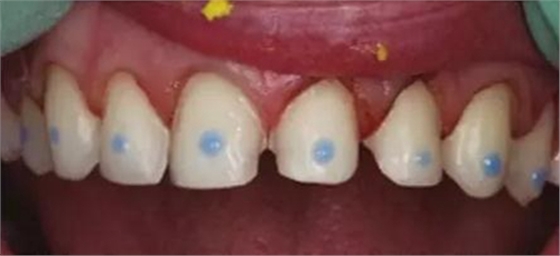

【貼面病例分享】

1.數(shù)據(jù)采集,術(shù)前牙齒形態(tài)

6.牙面處理

7.粘結(jié),需把牙列上貼面同時(shí)就位,同時(shí)用極小的粘結(jié)劑粘結(jié)固位每個(gè)貼面后,才開(kāi)始逐個(gè)粘結(jié)。

8.貼面完成